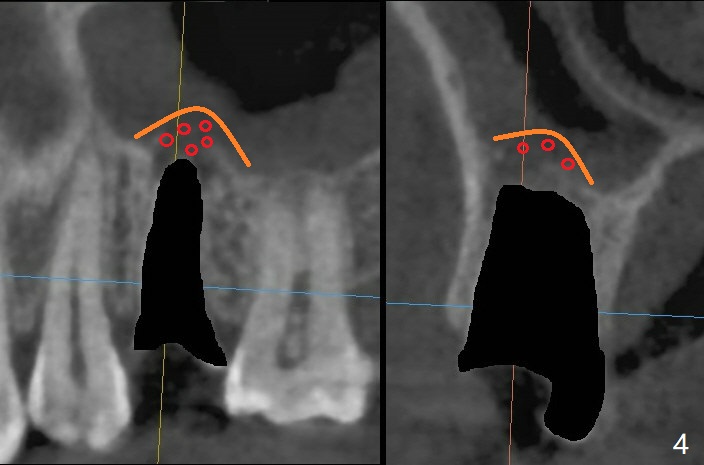

40岁女右上5树脂脱落,少许龋齿,近中边缘稍微龈下(图一:^),轻微叩痛(*)。经过商讨,她选择拔除植牙。CT检查显示上颌窦膜增厚(图二:*),为了减少术后上颌窦炎,第一,Z Pack(上呼吸道广谱抗菌素)和Medrol Dose Pack(激素)处方已开;第二,拔牙后(图三),将PRF膜推入上颌窦(图四:橘黄色),然后粘性骨块(红色圆圈);第三,植体长度刚好穿过窦底板(图五:11.5毫米)。Return to No Deviation 手术 No Neighboring Caries No Antibiotic 8, 10,30/31,19 Armaments 提升 Xin Wei, DDS, PhD, MS 1st edition 10/02/2020, last revision 03/28/2021